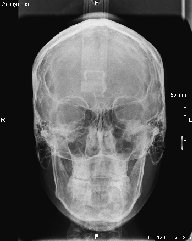

Algunos ejemplos de imágenes digitales

Pulse en las imágenes para ver la ampliación

14fte 1